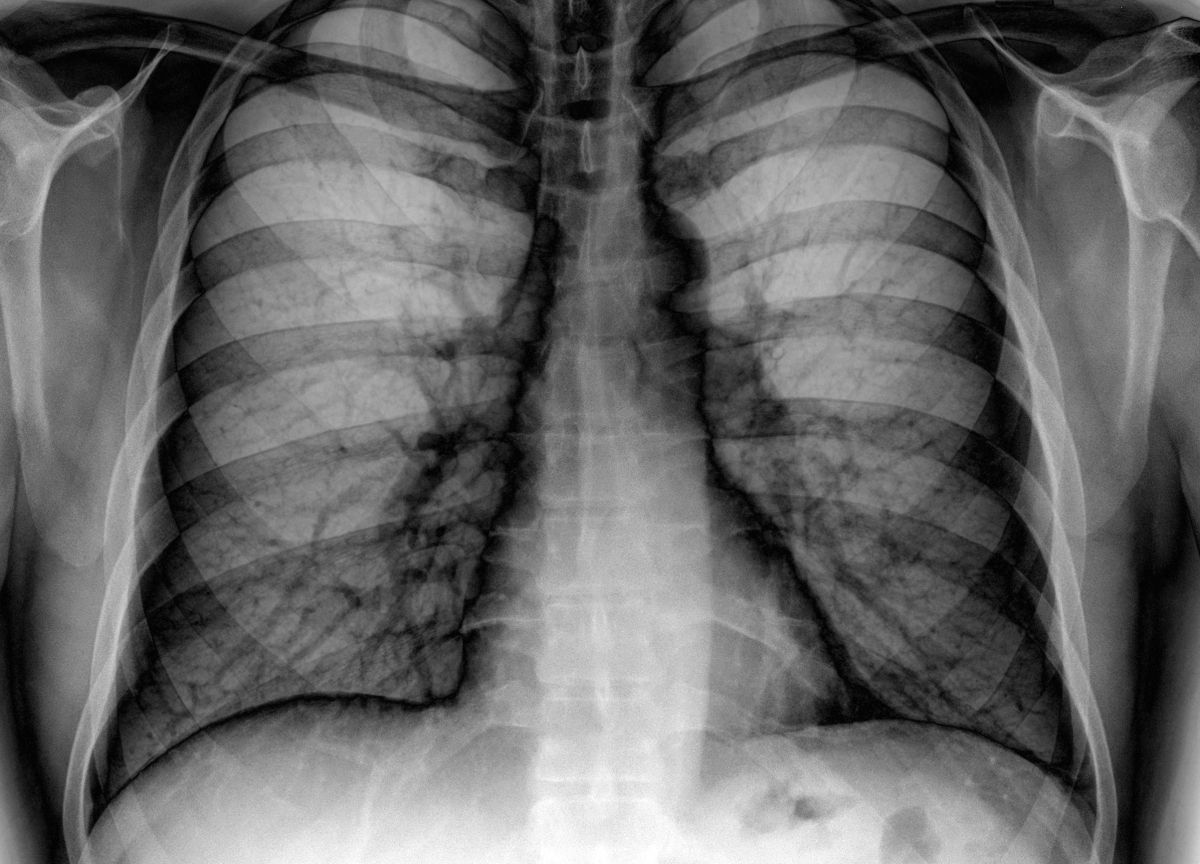

Raziskovalci z ameriške univerze v Teksasu so z deli pljuč dveh preminulih otrok – ena pljuča so razdelali do le kolagena in elastina, dveh glavnih sestavin vezivnega tkiva – ustvarili ogrodno strukturo, iz drugih pa pridobili potrebne celice.

Štiri tedne pozneje so imeli celotna človeška pljuča, postopek pa so uspešno ponovili. Ta metoda je bila razvita leta 2010, od takrat pa je že bila preizkušena na podganjih in prašičjih pljučih.